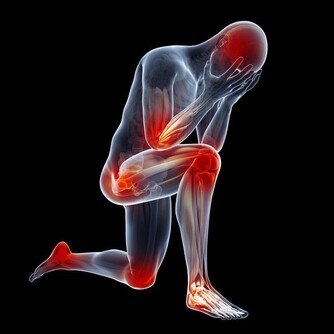

4、心腦血管疾病

高血壓或心臟病,嚴重的便秘,常因排便,腹壓增加,用力過度,精神緊張等因素,誘發或加重冠狀動脈供血不足,血壓暫時升高或突發腦出血,心肌梗死。